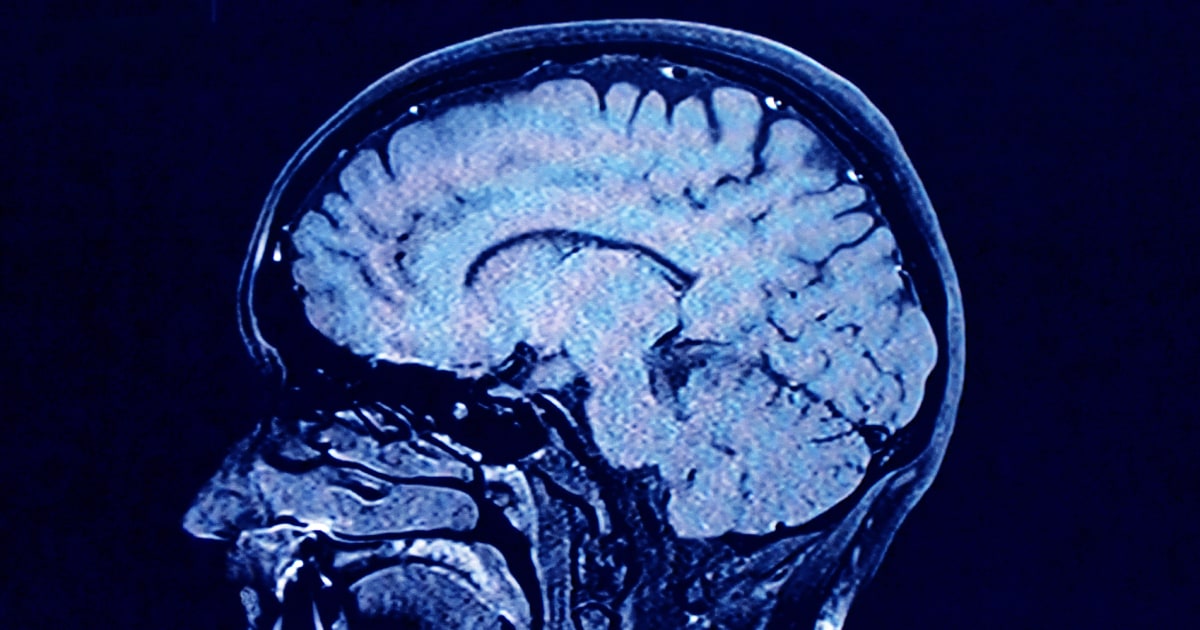

For their research, Mousley and her colleagues analyzed MRI diffusion scans — which are essentially images of how water molecules move within the brain — from about 3,800 people from age 0 to age 90. The goal was to map the neural connections across the average person’s brain at different stages in life.

In the brain, the bundles of nerve fibers that transfer signals are encapsulated in fatty tissue called myelin. Think of it like wiring or plumbing. Water molecules diffused in the brain tend to move in the direction of these fibers, rather than across them, meaning researchers can infer where the neural pathways are located.

Based on the MRI scans, the new study maps the neural network of an average person across a lifespan, determining where connections are strengthening or weakening. The five “epochs” it describes are based on the neural connections the researchers observed.